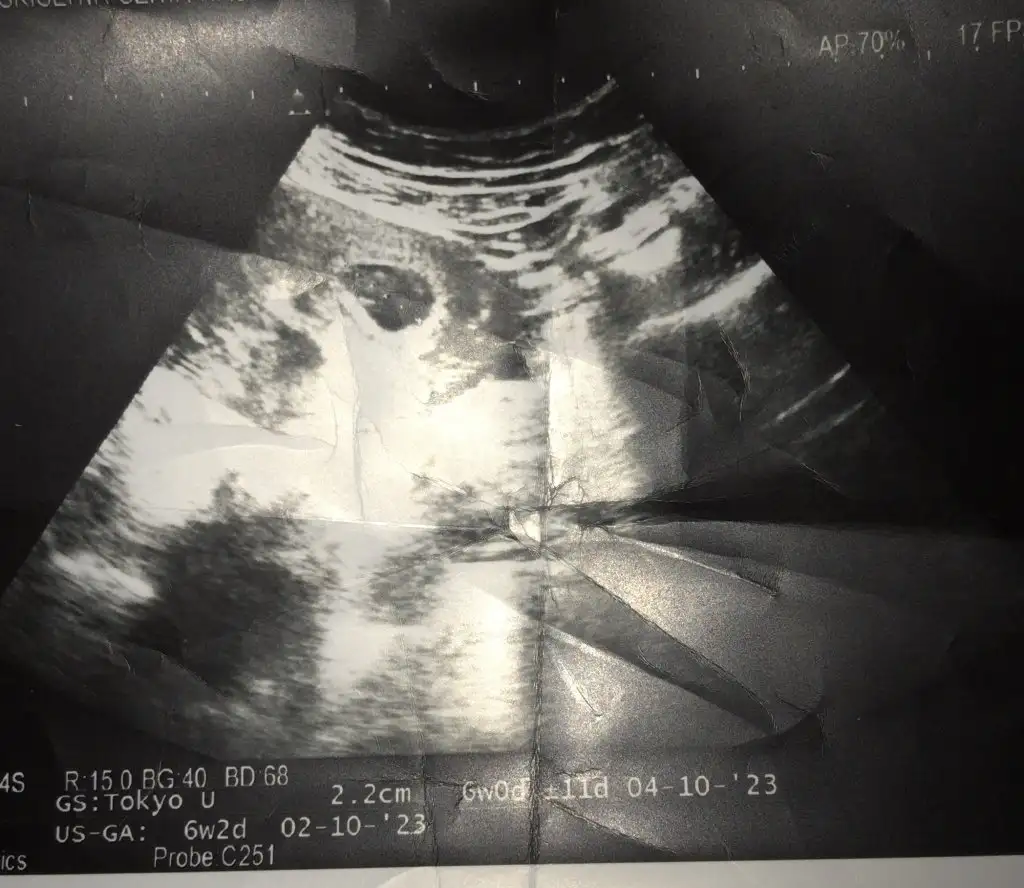

Banada yorum yaparmısınız karından 6 haftalıkKarındansa erkek vajinalse kız, şekil olarak erkek

6-7 haftalık ultrason resmini at canım ve karından mı vajinal mi onu yaz